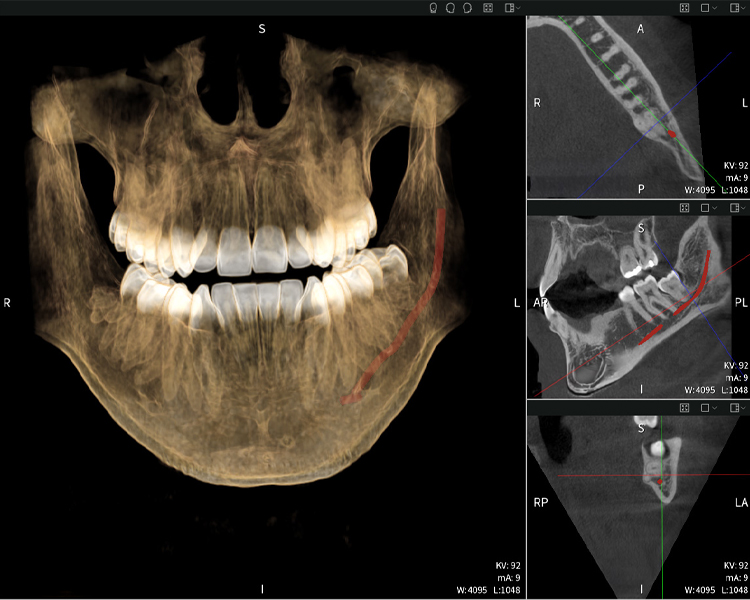

Abbildung b: Bildgebungsergebnisse von Seethrough Max vor einem schwarzen Hintergrund.

Abbildung b

Abbildung d: Bildgebungsergebnisse von Seethrough Max vor einem schwarzen Hintergrund.

Abbildung d

Abbildungen b–d zeigen verschiedene Ansichten einer 3D-Rekonstruktion des Unterkiefers und bieten eine umfassende Übersicht über die Anatomie des Unterkiefers, die Lage der Nerven im Verhältnis zu den Zähnen und ermöglichen die Beurteilung der Zahnsymmetrie und Ausrichtung.

Abbildung c: Bildgebungsergebnisse von Seethrough Max vor einem schwarzen Hintergrund.

Abbildung c

Abbildung d zeigt den bereits vorbehandelten Zahn 48, dessen Krone entfernt wurde und dessen Wurzeln nahe am Nerv belassen wurden, was das hohe Risiko einer Nervenschädigung verdeutlicht.